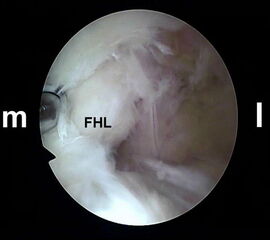

Abbildung Nr. 5-7

Über das laterale Portal wird ein 4,0 mm Arthroskop senkrecht nach ventral eingebracht mit der Zielrichtung auf den 1. Interdigitalraum. Zur Orientierung kann mit dem stumpfen Wechselstab zunächst der Kontakt zum Knochen getastet werden. Es lassen sich so auch die dorsale Tibiakante, der Proc. posterior des Talus und die craniale Begrenzung des Kalkaneus identifizieren. Ist das Arthroskop über das laterale Portal eingeführt, wird die Blickrichtung nach lateral ausgerichtet. Von medial wird ein Weichteilshaver eingeführt, dessen Arbeitsöffnung nach ebenfalls lateral weist. Die Instrumente werden in der Weise trianguliert, dass die Shaverspitze unmittelbar vor dem Arthroskop identifiziert werden kann (rechte Seite, m=medial, l=lateral).